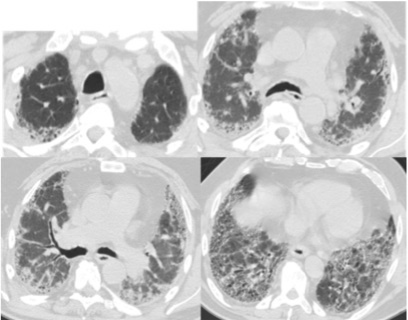

Figure 1: HRCT images are showing the "propeller blade" distribution (white arrows) in IPF. View Figure 1

Figure 2: HRCT images are showing the "propeller blade" distribution (white arrows) in patient with IPF. View Figure 2

Totally 51 patients were included in this study; 35 (68.6%) were male and 16 (31.4%) were female. The mean age was 70.8 years (min, 50-max, 86). The mean FVC, FEV1 and FEV1/FVC were 1970 ml (53%), 1860 ml (63%) and 94.4%, respectively. The diagnostic efficacy of chest roentgenograph was 58.7% in patients with IPF. The radiologic progression during several years in patients with IPF were shown in Figure 3, Figure 4, Figure 5 and Figure 6. The most common comorbidity was malignancy (10.8%) in patients with IPF and lung cancer with IPF was shown in Figure 7. The number of cases with "propeller blade" distribution (PBD) (Figure 1 and Figure 2) was 32 (62.7%). The acute attack of IPF was observed in 10 (19.6%) patients. Radiologic findings of acute exacerbation in patients with IPF were showed in Figure 8, Figure 9 and Figure 10. HRCT patterns in patients with idiopathic pulmonary fibrosis were demonstrated in Figure 11 and Figure 12.

Another HRCT characteristic that can be helpful in making a diagnosis of UIP is the so-called "propeller blade" distribution (PBD). This variant gets its name from the fact that, when seen on sequential axial images from caudal to cranial, the honeycombing or reticulation changes from being predominantly posterior to anterior [11]. In our study, the rate of PB distribution was 62.7%. We think that the definition of IP giraffe pattern in IPF. Is similar to the patterns of giraffes in IPF and that radiological confusion in these patients can be explained a little. Each giraffe has its own pattern style. In this style, each giraffe has its own particular order. Although there are some disagreements about the exact number of subtypes in the scientific world, there are nine giraffe patterns. These are Reticulated, Kordofan, Nubian, Angola, South Africa or Cape, Rothschild or Ugandan, West Africa or Nigerian, Thornicroft and Masai (Figure 13).